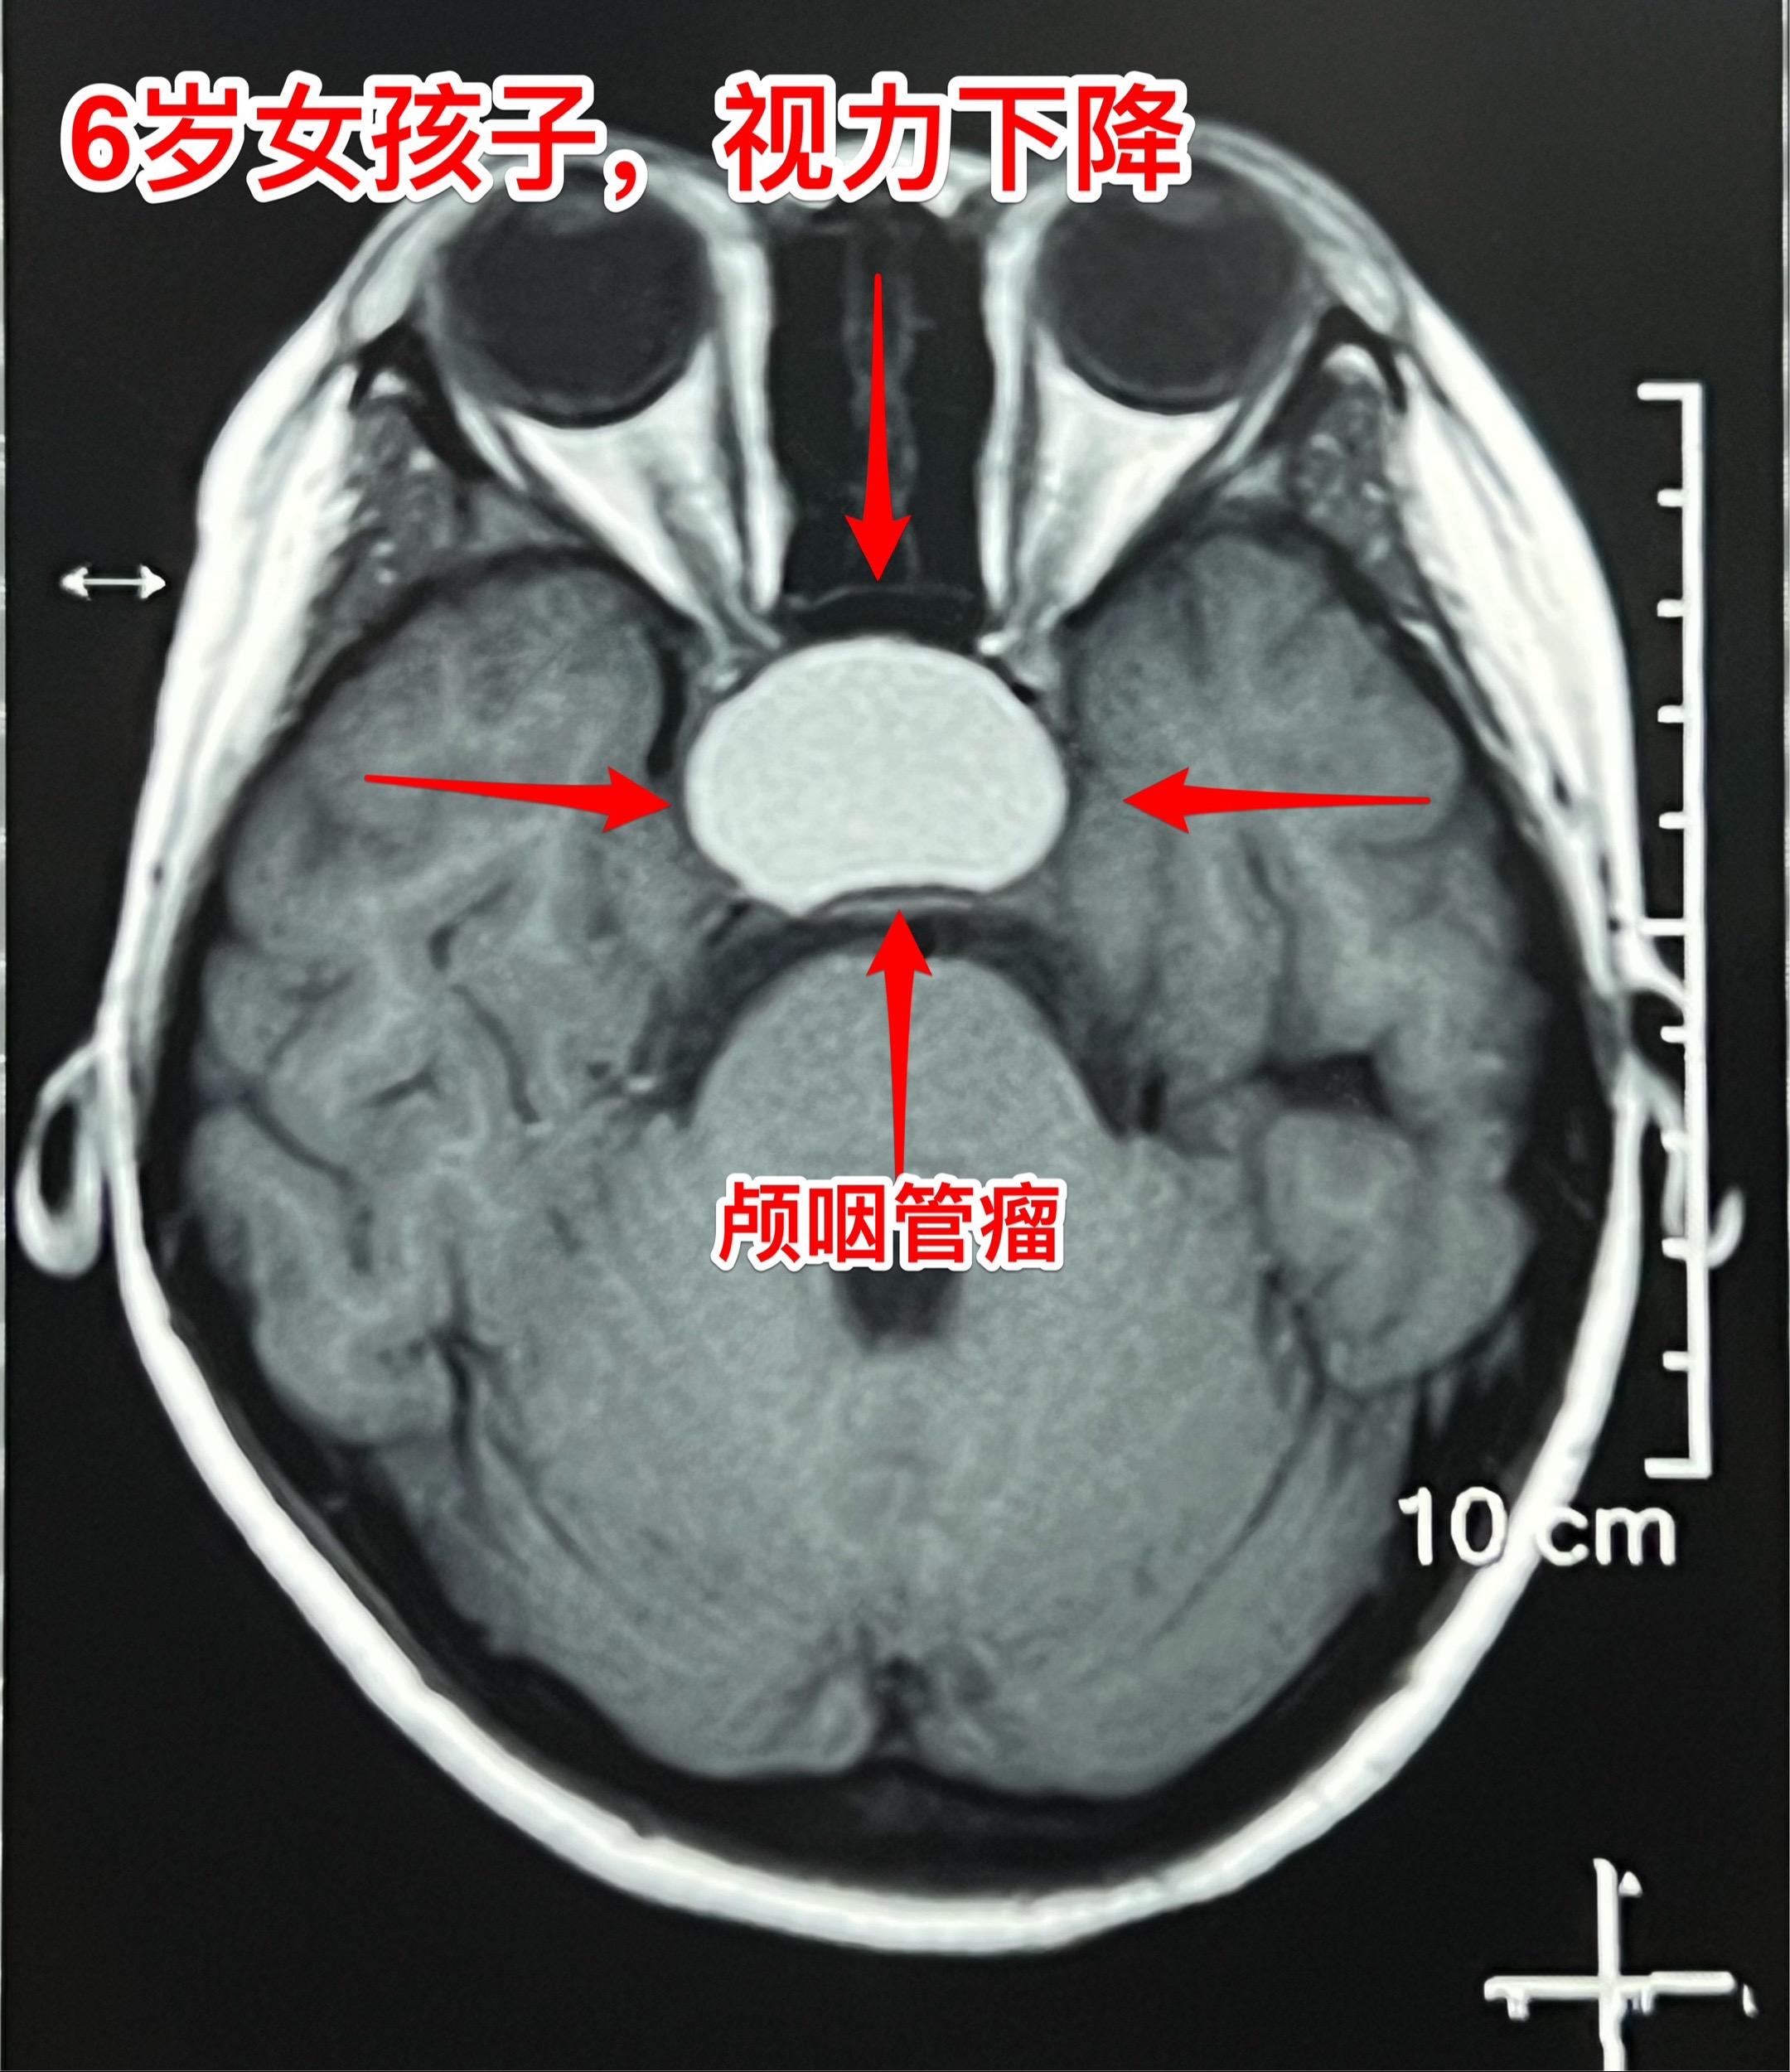

小学生的视力家长一定要关注。小学生因岁数小,对视力下降很可能并不知道表述。所以家长一定要密切观察孩子的视力变化。如果 孩子在很近距离才能看清书上的字,或者看电视距离时喜欢靠近电视机很近才能看清楚,家长就要想到孩子的视力出了问题。我在之前的视频中曾经提到过类似的悲惨事件。 今天说的是六岁郑州小女孩,于2月22日在家写字时居然无法看清作业本上的方格了!家长这才发现孩子的视力很差了,快接近失明了。 2月23日行磁共振检查,发现鞍区肿瘤。3月25日行CT检查,发现肿瘤有钙化,可以确诊